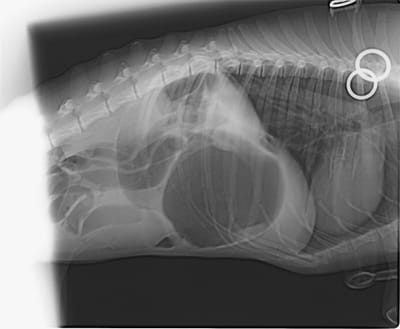

בדיקות אולטראסאונד. ד"ר אסף אלקלעי מוסמך אירופאי בהדמיה GPCert-DI ובעל ניסיון רב בסריקות US

בבית החולים רנטגן דיגיטלי תשובות במקום!